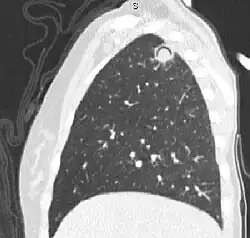

Air crescent sign

In radiology, the air crescent sign (also called the Monad sign[1]) is a finding on chest radiograph and computed tomography that is crescenteric and radiolucent, due to a lung cavity that is filled with air and has a round radiopaque mass.[2] Classically, it is due to an aspergilloma, a form of aspergillosis, that occurs when the fungus Aspergillus grows in a cavity in the lung.[3]